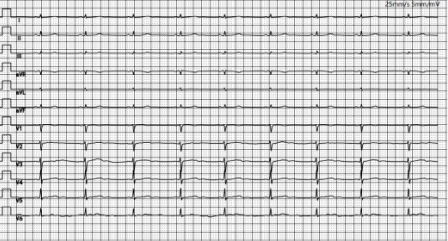

消融前心电图

消融后心电图

消融前后心电图对比见早搏明显消失。